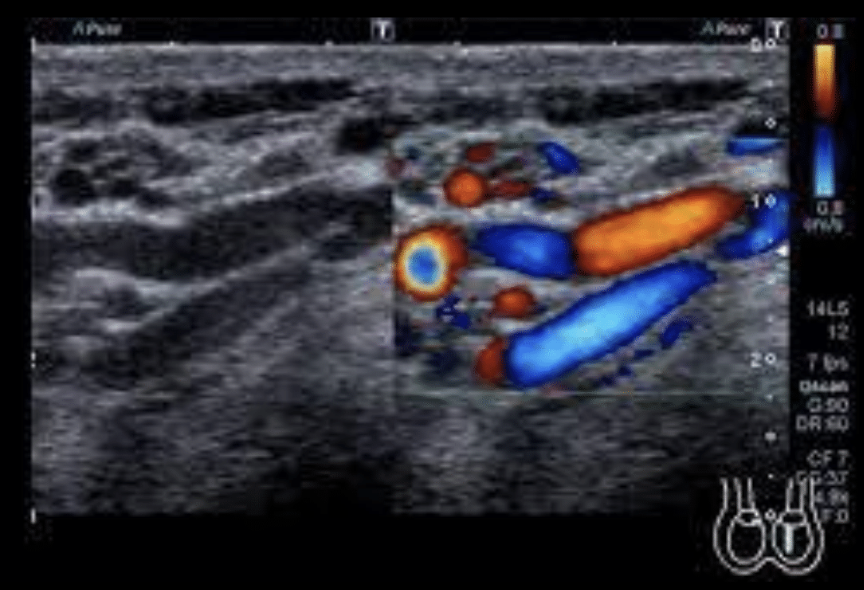

23

Q

Doppler en arterias uterinas

A

Riesgo de preeclampsia

24

Doppler en plexo pampiniforme (testículos)